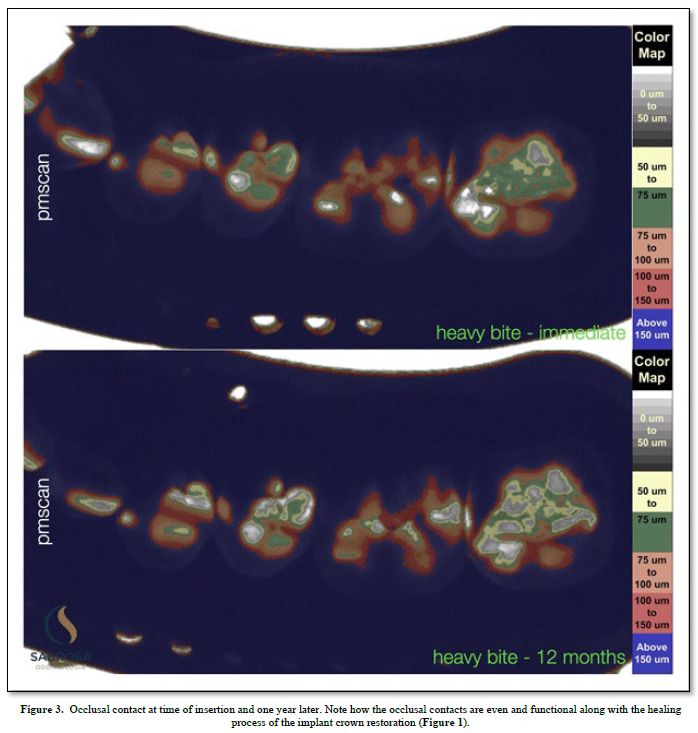

Proprioception is used to navigate space in order for a subject to find a place to make physical contact. (1) An implant with no periodontal housing exhibits little or no proprioception. It has no periodontal housing and no touch or pressure sensors. An opposing functioning tooth with periodontal support is proprioceptive. It is touch sensitive (2). The pressure sensors detect motion and help to reposition and maintain the tooth in a functioning occlusal position. There is little or no information concerning implant proprioception. In a functioning dentition teeth find their position by adjusting to the existing teeth in occlusion. An under occluded implant crown cannot adapt to an existing occlusion without planned occlusal contact guidance. Positional direction and intensity of contact are left to chance. We, as humans, have five senses one of which is touch. Sharks have six senses one of which is touch from a distance (3). Weak electrical signals are used to make contact from afar. Humans can not touch without making physical contact. An implant crown that is under articulated cannot fit into an opposing dentition without making occlusal contact. Total implant placement procedures and restorative healing results are shown (Figure 1). Without implant restorative occlusal contact adjacent teeth and the surrounding dentition adapt to an altered occlusion. Stress distribution is uneven because fewer teeth maintain the occlusal load. Missing limb syndrome where the patient assumes limb retention upon fitting a prosthetic device may be applied to replacing missing teeth where the patient upon tooth replacement immediately assumes past functioning habits. In this case, as shown, tooth and jaw movements related to an altered occlusion are slight but tooth movements are discernible. The occlusal patterns have shifted. There is an uneven amount of occlusal contact upon the second molar (Figure 2). One year later the occlusal contact areas are more evenly distributed. The implant restoration is in functional occlusion. The second molar now fits into the occlusal scheme as does the first molar implant restoration. The teeth have been realigned (Figure 3). In order to plan the occlusion of this implant the clinician (CES) adjusted the surface of the milled zirconia crown (Cerec) prior to completion so that it would just make occlusal contacts upon hard closure (Figure 2). Clinical acumen dictates how much occlusal clearance is required. It is estimated that teeth intrude up to 100 microns upon occlusal loading (3). We assume that when the tooth is fully loaded it will make occlusal contact with its antagonist but when not loaded it will not make contact (4) (Figure 2). To verify contact and non-contact we make a silicone inter occlusal record at the time of insertion (5). The impression is removed and immediately processed using a specially made occlusal scan which includes a direct current light box positioned six inches from an enclosed overhead camera which is connected to an image producing means for recording and interpreting various thicknesses of impression material. The results using image analysis (Image J) can be assessed numerically or viewed using assigned colors that relate to the numbers (6). Two hundred fifty-six pixels is the baseline and the color is white (contact).

A reduction in compressed impression material as shown by using associated colors represents near and far areas of occlusal contact. Proprioception has become a discerning factor. If the implant crown does not have minimal contact upon placement, it may not adjust to the opposing tooth. Proprioception tells your brain where your body parts are located in relation to one another. It works to guide motor skills and to control movements.